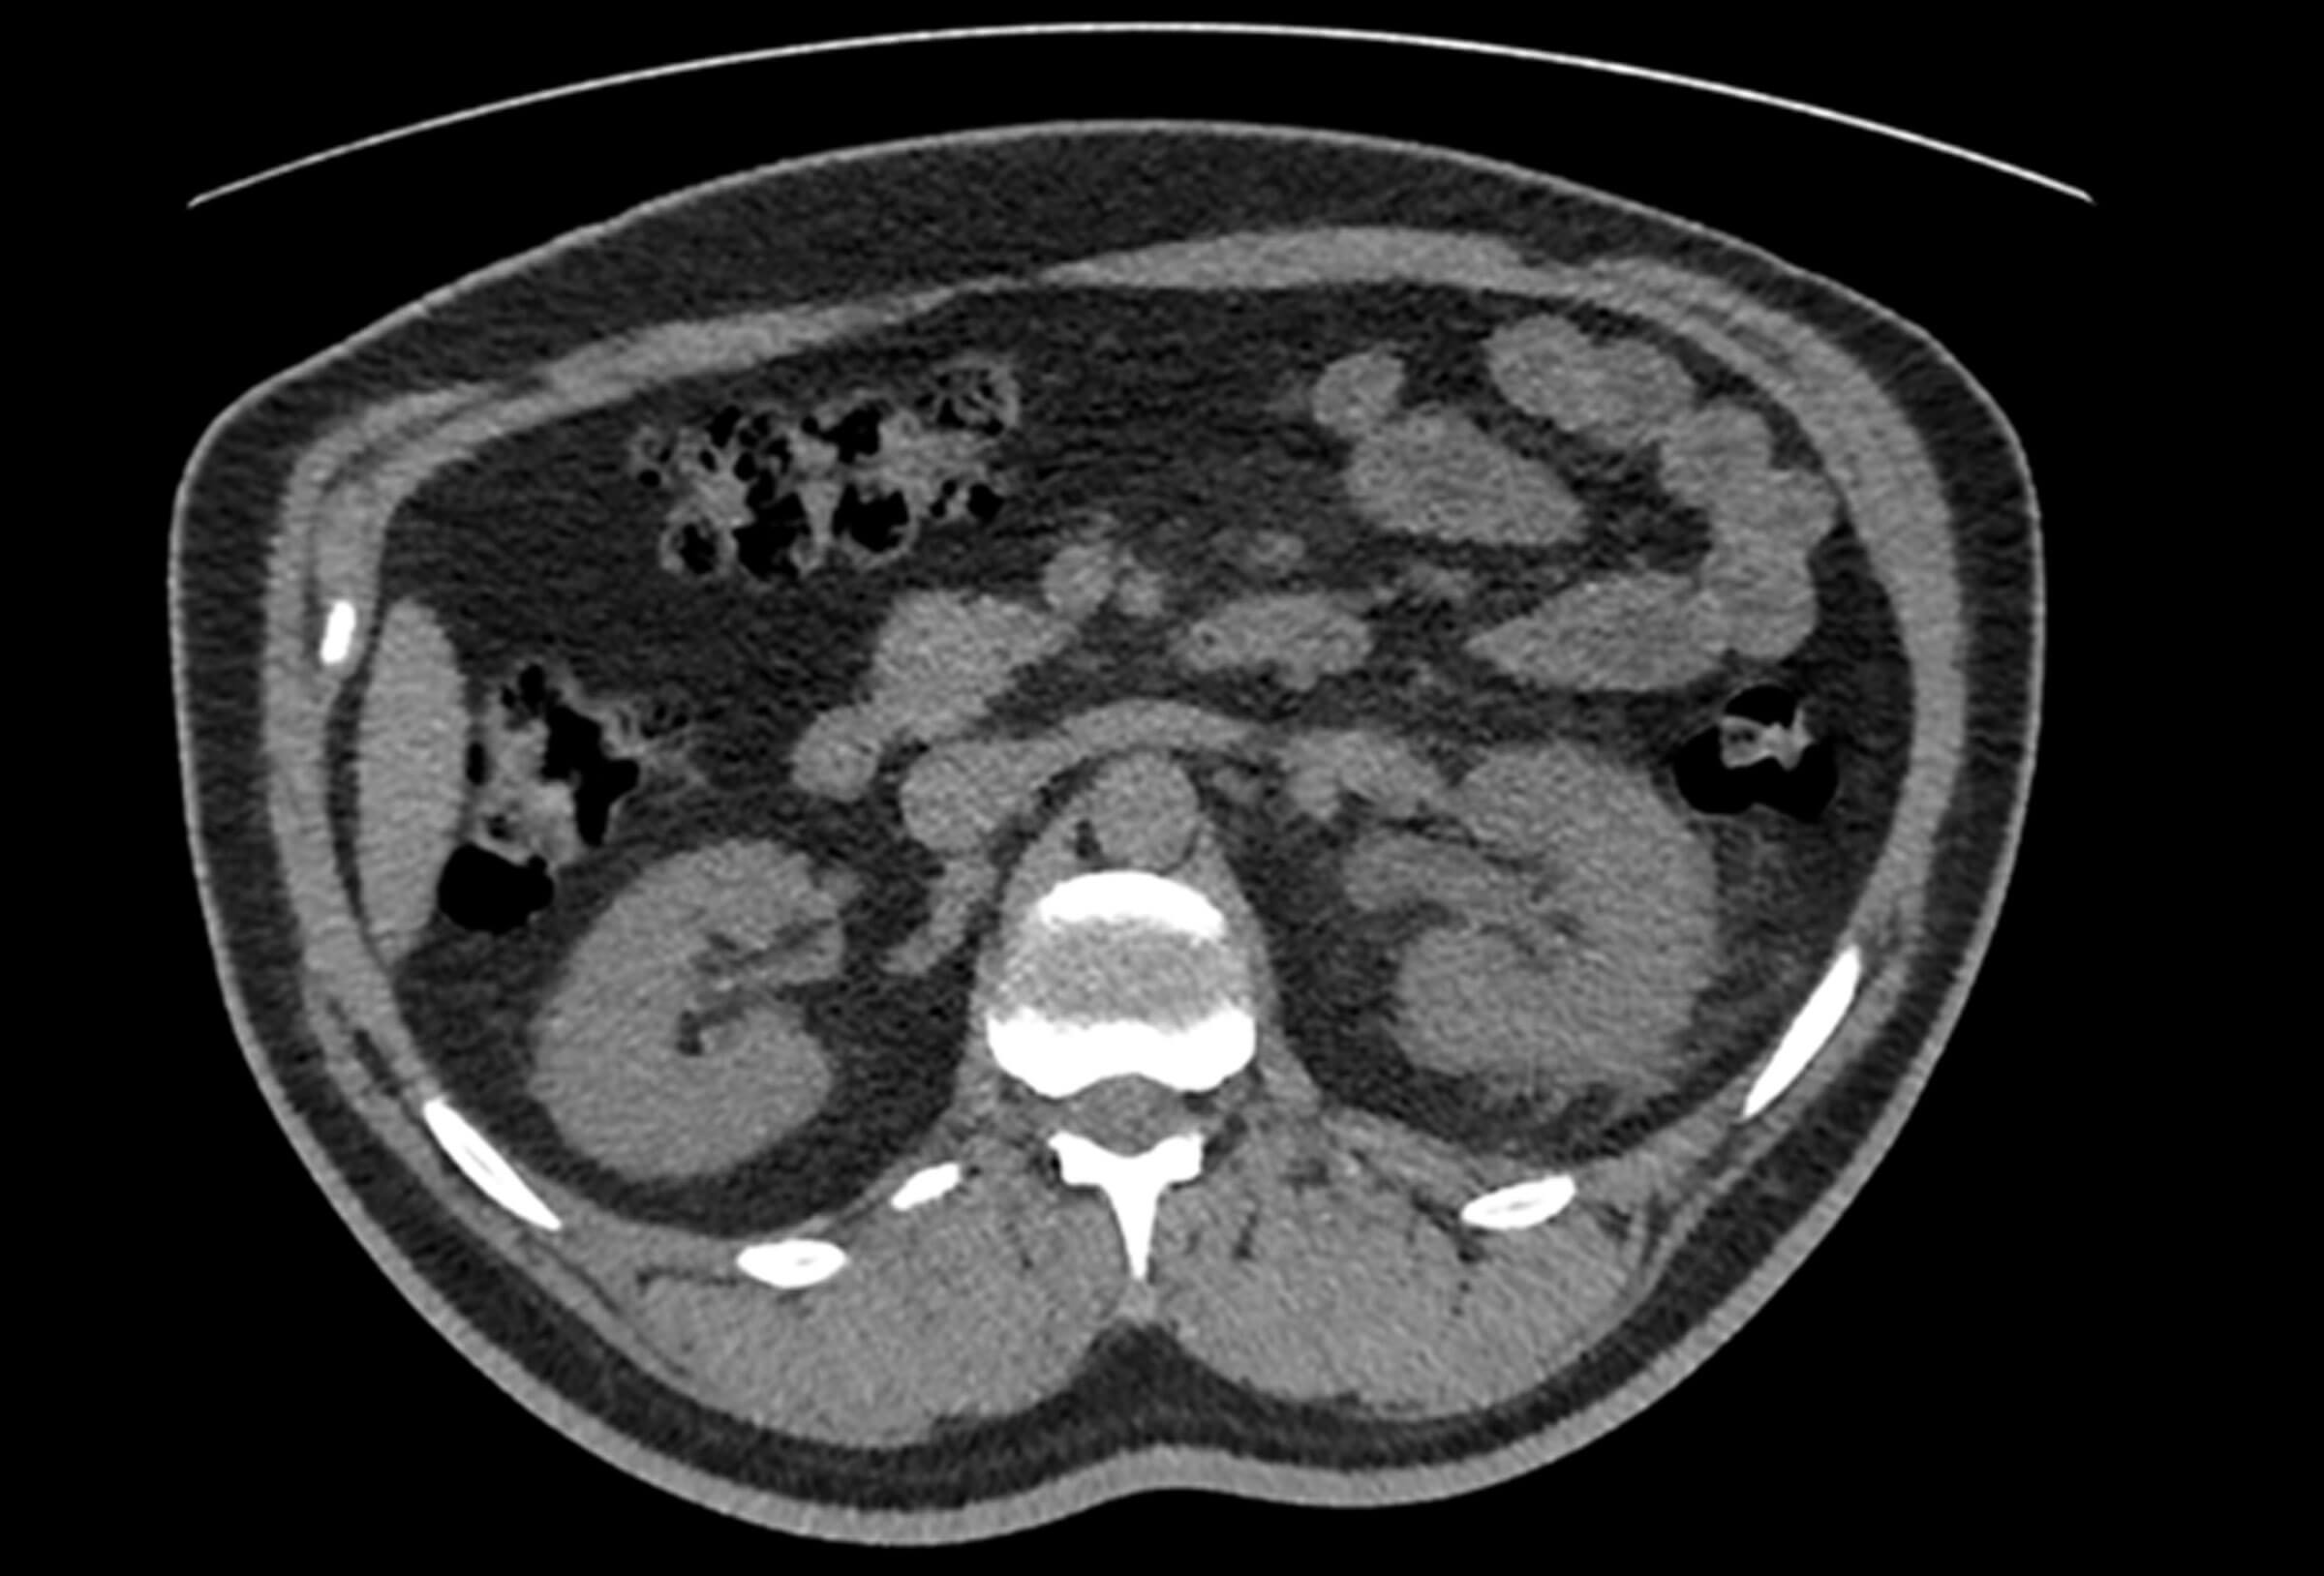

Urolithiasis 1 – ureteric colic

- Click for Part 2 and Part 3 on this topic - Case scenario A 45-year-old male presents to Accident & Emergency with two days of intermittent, severe, left-sided loin to groin pain and multiple episodes of vomiting. He undergoes...